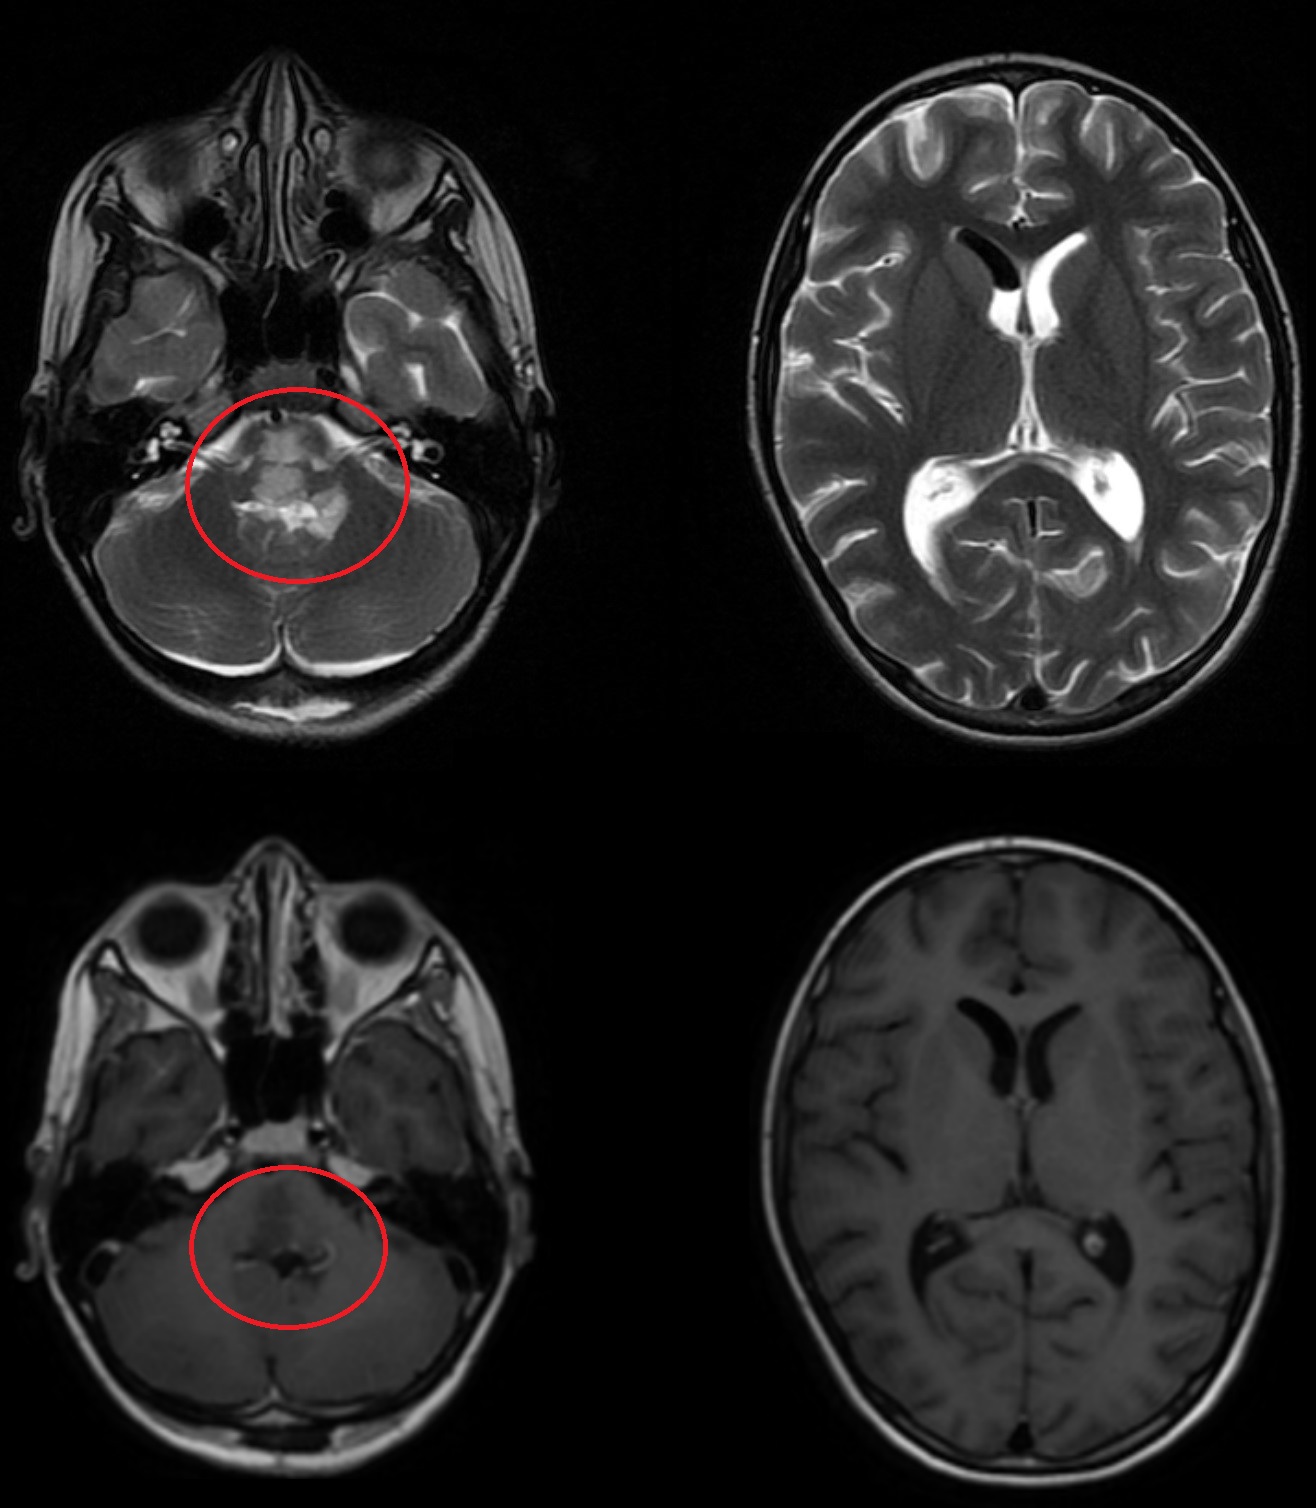

Результаты. У 19 пациентов (50 % от 38 прошедших биопсию) по данным иммуногистохимического анализа послеоперационного материала была выявлена мутация К27М в гене H3F3A. У 6 (15 %) пациентов из 38 МРТ в сроки от 2 до 5 мес (медиана – 4,5 мес) после окончания лучевой терапии выявлено нехарактерное прогрессирование ДСГ в виде метастазирования по желудочковой системе головного мозга. У остальных пациентов когорты исследования, не проходивших процедуру биопсии, подобный характер прогрессирования не наблюдался (p<0,002): у них, как правило, отмечался продолженный рост опухоли (n=96), у 4 больных диагностировано лептоменингеальное метастазирование по спинному мозгу.

Заключение. Нами выявлены случаи нетипичного прогрессирования ДСГ в виде метастазирования по желудочковой системе у детей после открытой биопсии опухоли. Есть основания полагать, что биопсия могла способствовать диссеминации ДСГ по ликворным пространствам. Необходим поиск альтернативных методов оценки молекулярно-генетических характеристик ДСГ.